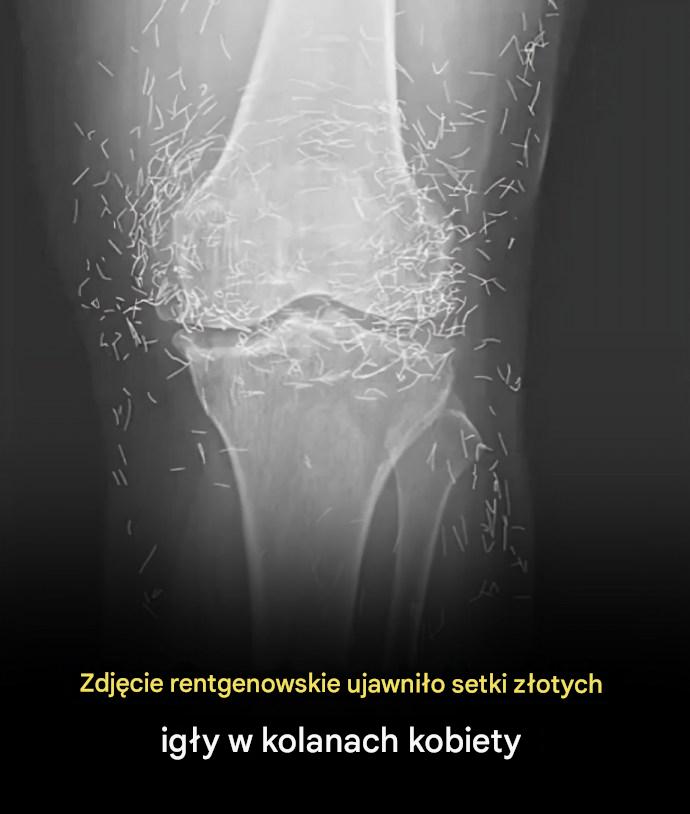

Kiedy lekarze zbadali zdjęcie rentgenowskie kolan starszej kobiety cierpiącej na silne bóle stawów, odkryli prawdziwą żyłę złota: setki maleńkich złotych igieł do akupunktury pozostawionych w jej tkankach.

U 65-letniej Koreanki z Południa zdiagnozowano wcześniej chorobę zwyrodnieniową stawów, schorzenie, w którym chrząstka i kość w stawach ulegają zniszczeniu, powodując ból i sztywność. Jednak gdy leki przeciwbólowe i przeciwzapalne nie przyniosły ulgi …